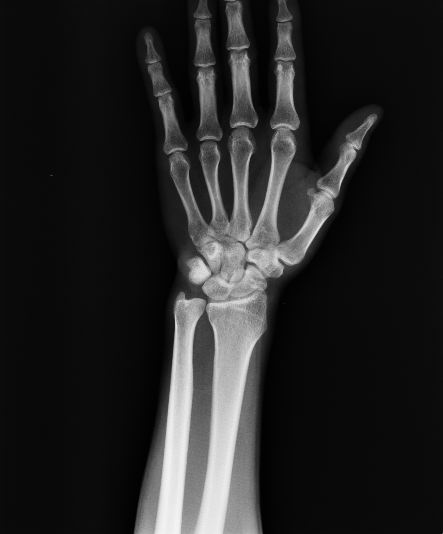

以下是引用杀毒软件在2008-9-4 17:41:00的发言:[br]考虑----舟骨囊肿